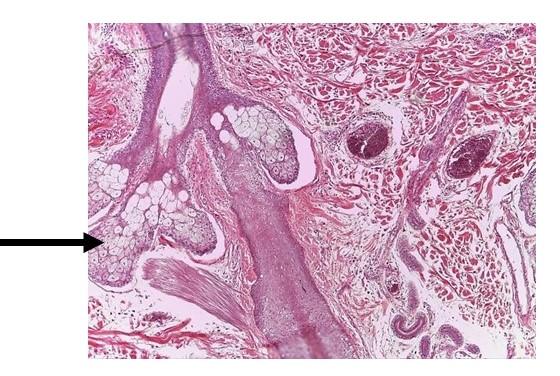

Identify the general layer of skin indicated.

epidermis

Identify the specific gland indicated.

sebaceous gland

Identify the general layer of the skin indicated.

epidermis